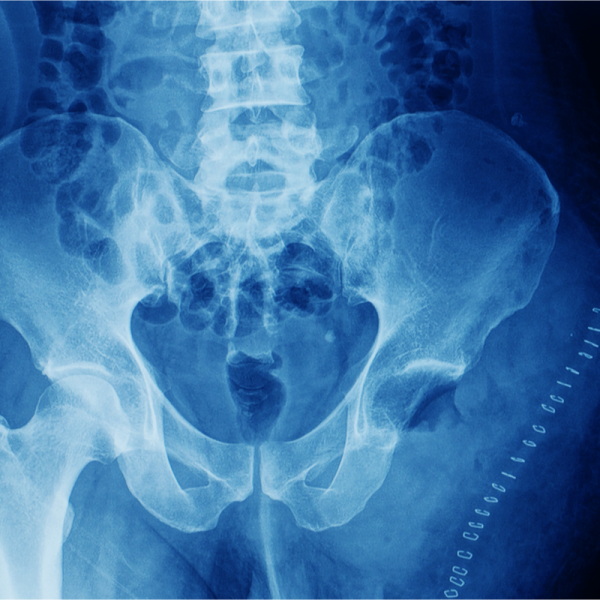

Ein Chondrosarkom ist ein bösartiger (maligne) knöcherner Tumor, der aus embryonalen, oder ausgereiftem Knorpelgewebe hervorgeht, und sich vor allem am Becken, an der Hüfte oder an der Schulter ausbildet.

Ein Chondrosarkom kann, wie andere Krebserkrankungen auch, durch bildgebende Verfahren sichtbar dargestellt werden. Neben einer Magnetresonanztomografie (MRT) kann hierzu auch eine Computertomografie (CT) zur Anwendung kommen, nachdem der Verdacht auf ein Chondrosarkom vorliegt. In vielen Fällen wird das Chondrosarkom jedoch auch zufällig diagnostiziert. Innerhalb eines CTs wird das Chondrosarkom als Erosion der Knochen sichtbar und weist oftmals Kalkablagerungen auf. Innerhalb des MRTs hat der Tumor auffällige wabenförmige Muster.